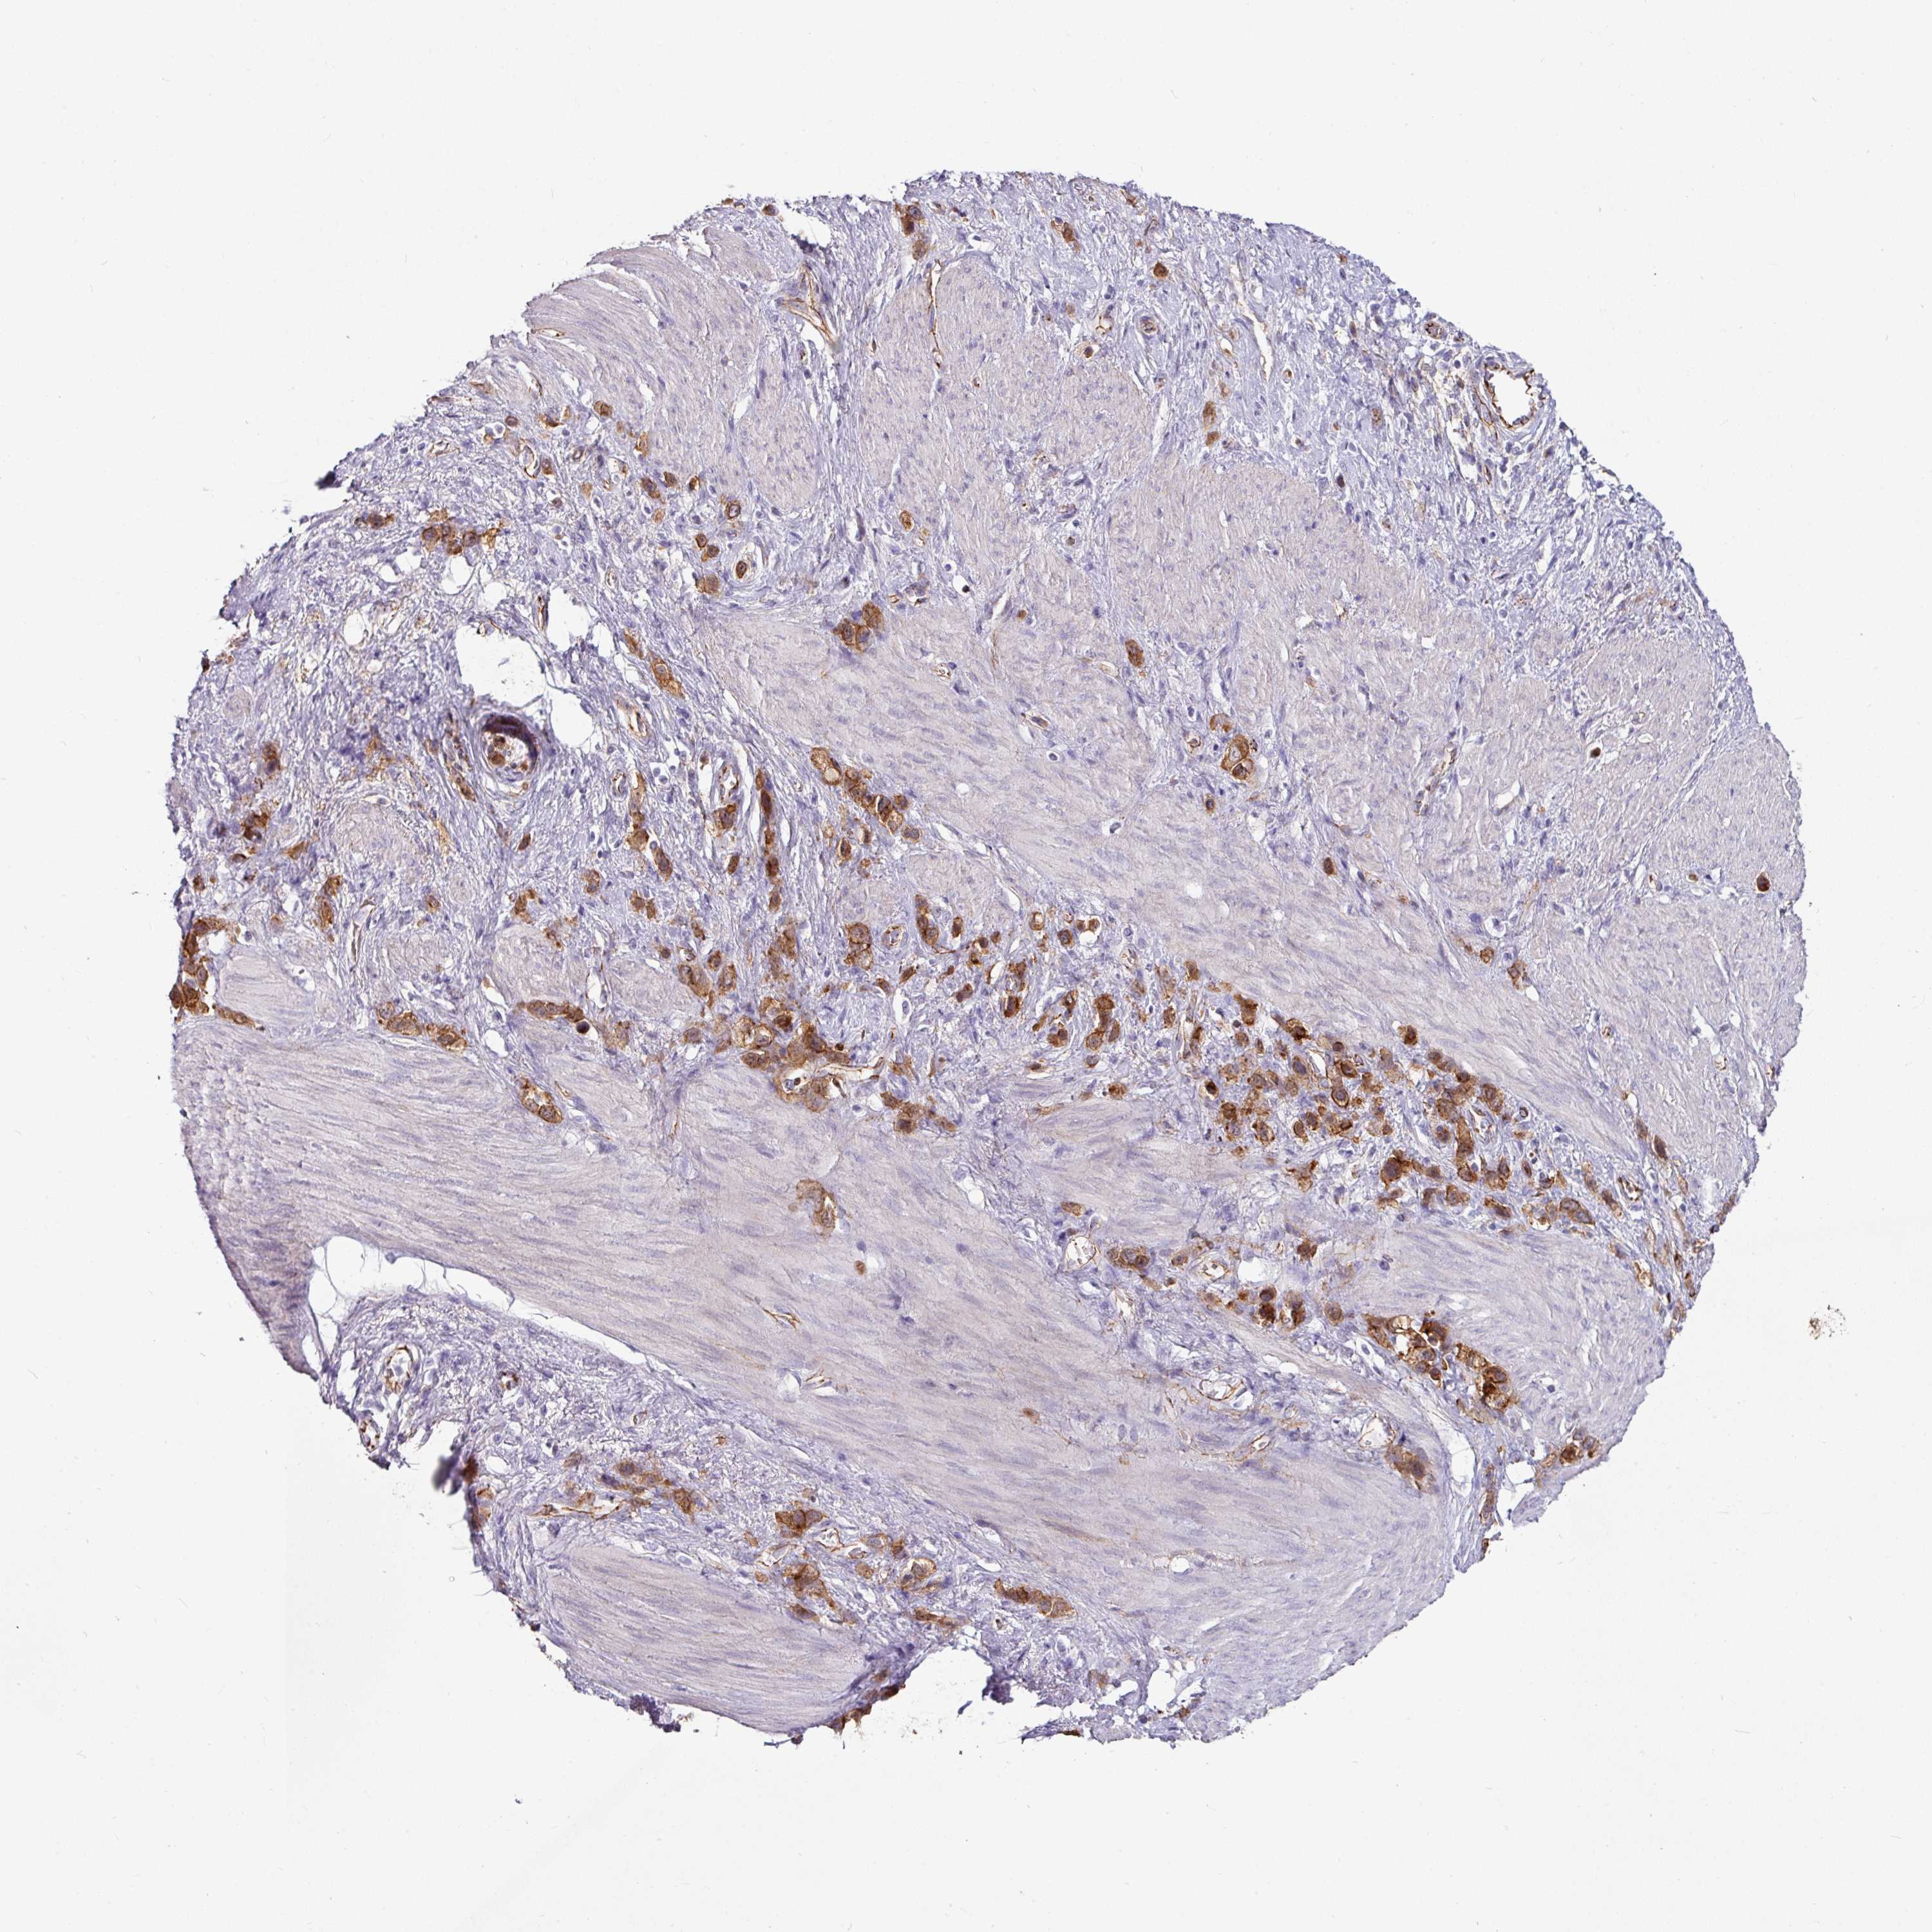

STOMACH CANCER - Protein expressioni

A mouse-over function shows sample information and annotation data. Click on an image to view it in a full screen mode. Samples can be filtered based on level of antibody staining by selecting one or several of the following categories: high, medium, low and not detected. The assay and annotation is described here.

Note that samples used for immunohistochemistry by the Human Protein Atlas do not correspond to samples in the TCGA dataset.

Antibody stainingi

Antibody staining in the annotated cell types in the current human tissue is reported as not detected, low, medium, or high, based on conventional immunohistochemistry profiling in selected tissues. This score is based on the combination of the staining intensity and fraction of stained cells.

Each image is clickable and will lead to virtual microscopy that enables deeper exploration of all samples and also displays staining intensity scores, fraction scores and subcellular localization as well as patient and tissue information for each sample.

Antibody HPA032047

Antibody CAB002139

Staining

High

Medium

Low

Not detected

Intensity

Strong

Moderate

Weak

Negative

Quantity

>75%

75%-25%

<25%

None

Location

Nuclear

Cytoplasmic/membranous

Cytoplasmic/membranous,nuclear

Adenocarcinoma, NOS